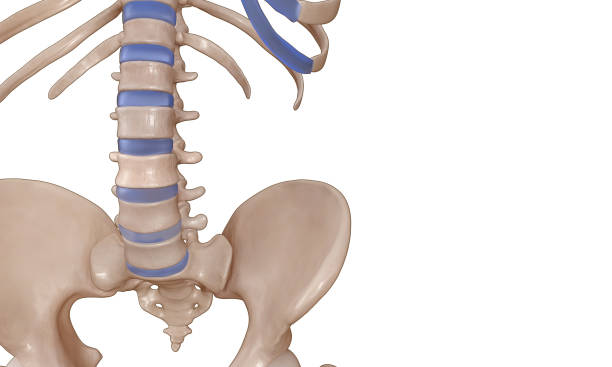

척추의 모양은 S자형이며 요추의 중립 자세는 C자형입니다. 그러나 햄스트링이 단축되면 골반이 뒤로 넘어가게 되어 후방경사 상태가 되며, 이로 인해 요추 전만이 감소합니다. 햄스트링이 항상 단축되어 있는 상태에서 요추 전만 자세를 유지하려고 하면 척추 근육과 인대에 부하가 증가하고, 결과적으로 척추 관절의 불안정성과 통증의 원인이 될 수 있습니다.

요추 전만은 허리디스크 치료와 예방에서 핵심적인 역할을 합니다. 요추 전만을 만들면 디스크의 압력이 감소하고 허리디스크 증상을 완화할 수 있습니다. 이를 위한 두 가지 자세가 있습니다.

오리 궁둥이 방법은 골반을 앞으로 돌리면서 엉덩이를 뒤로 빼는 자세입니다. 이 자세를 취하면 요추 전만 곡선을 만들게 됩니다.

당당한 가슴 방법은 골반을 그대로 고정하고 척추의 뒷부분만을 뒤로 젖혀 요추 전만 각도를 만드는 자세입니다. 이 자세는 상체 무게가 허리 뒤로 떨어지게 되어 디스크에 압력을 덜 가하게 합니다.